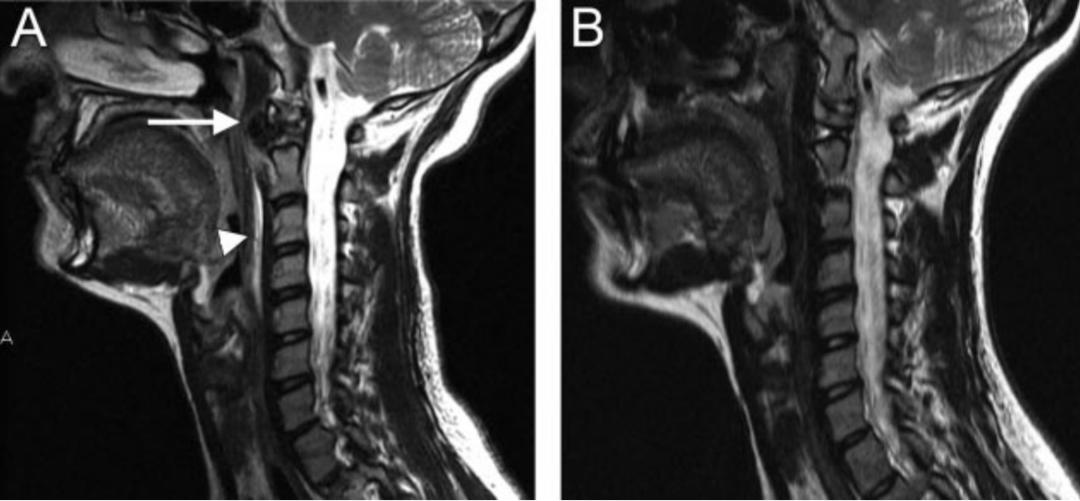

36岁女性,急性颈痛、吞咽困难伴颈部僵硬,MRI示C1-2前部颈长肌增厚呈低信号,提示钙化(长箭头)和C1-4椎前积液(无线箭头),经类固醇和止痛药治疗8天后症状消失,复查MRI提示上述表现消失。(PMID: 18765656)

C1-2前侧低信号(无线箭头)和C1-5椎前水肿(长箭头)